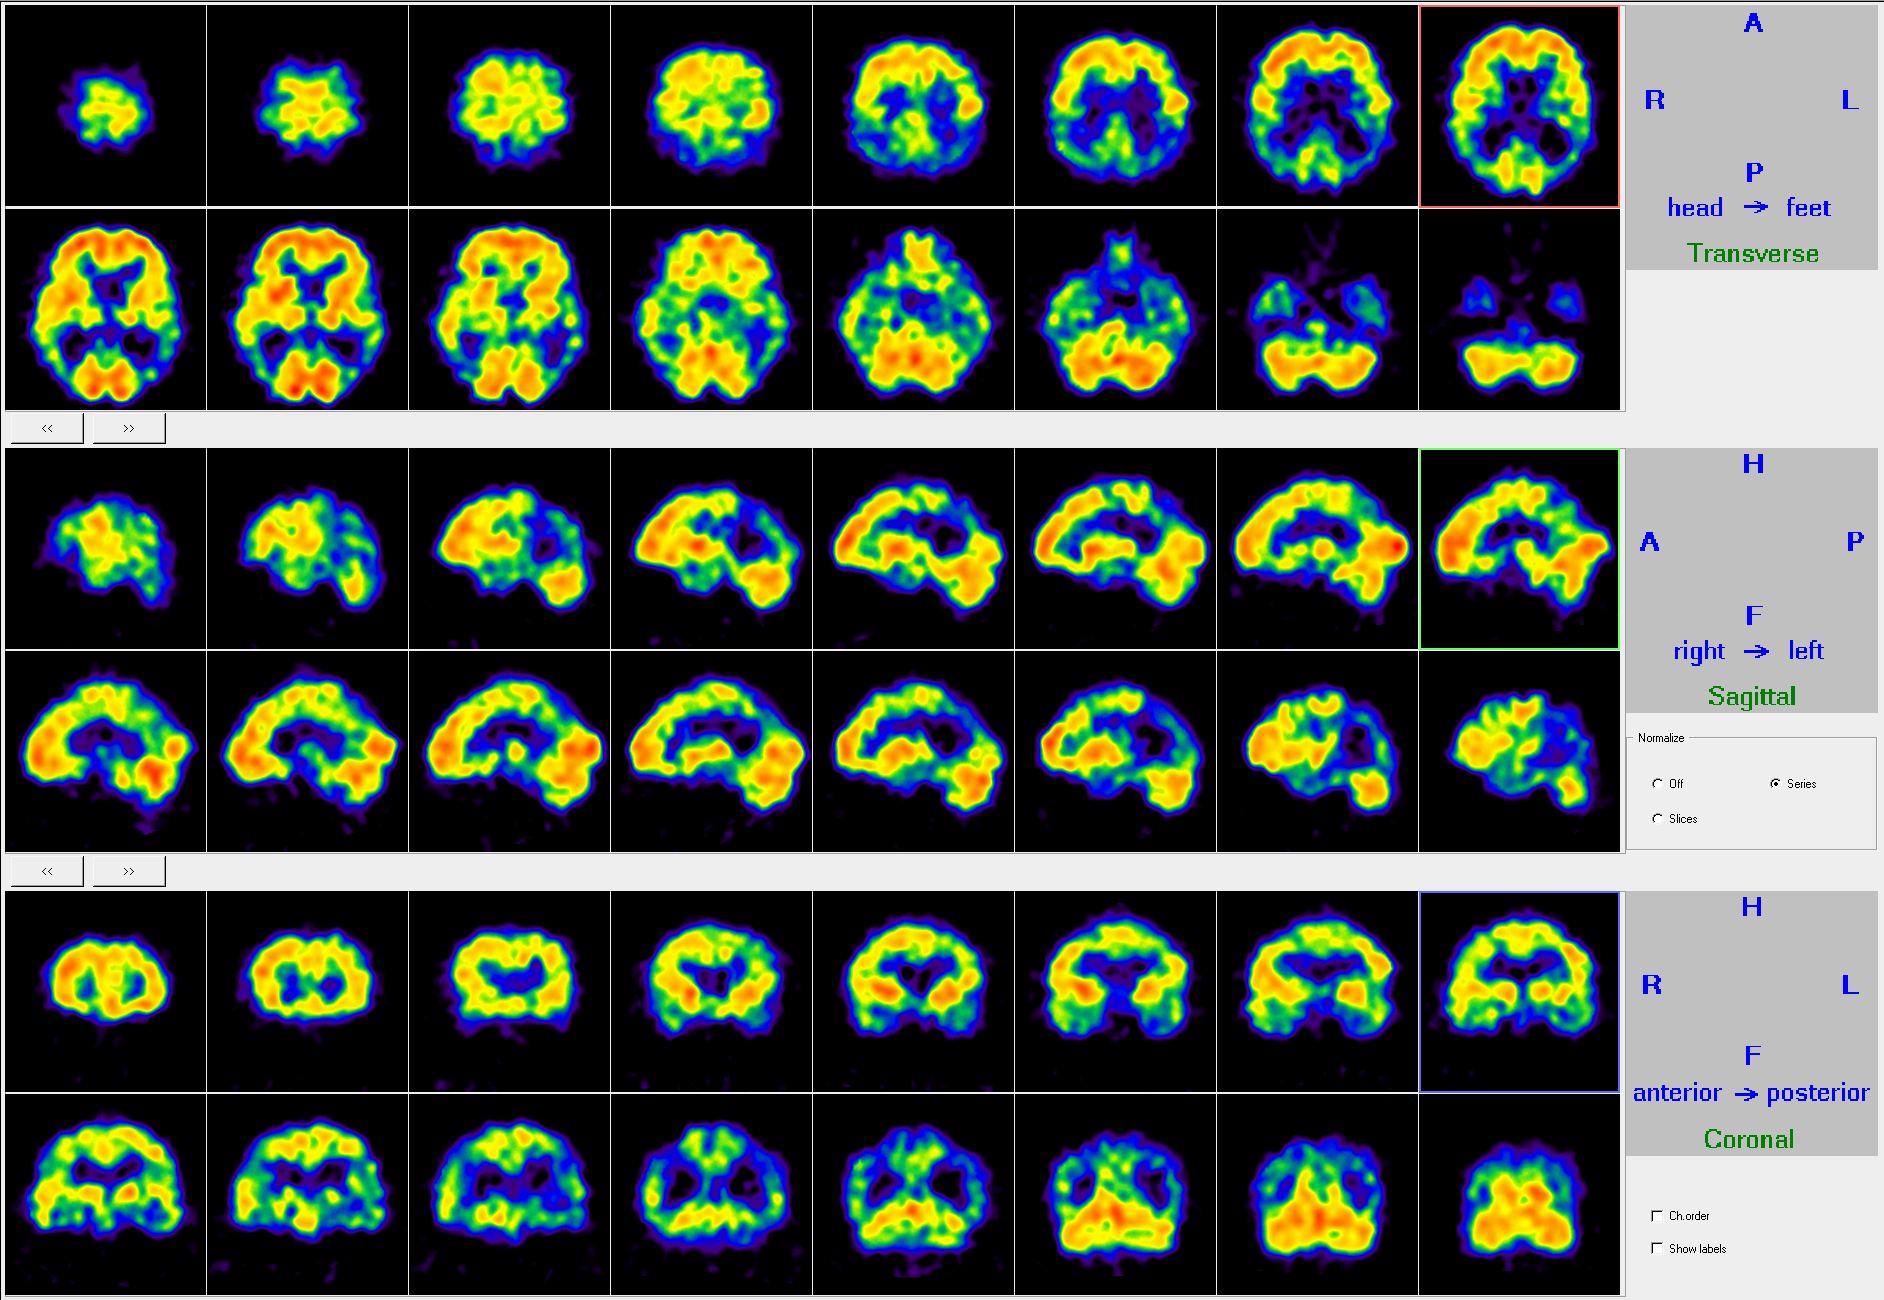

During functional brain mapping regional cerebral blood flow (rcbf) or glucose metabolism indicates neuronal activity. In rcbf SPECT measurements, the so called diffusible radiotracers are used. These pass through the blood-brain barrier. (They are either 99mTc labeled hexamethylpropyleneamine oxime, HMPAO or ethyl cysteinate dimer, ECD.) The radiotracers accumulate in the brain tissue proportional to the blood flow, through an entrapment mechanism. The sole energy source of the brain is glucose. Its metabolism can be depicted with FDG-PET examinations. Because of the entrapment mechanism, FDG accumulation is going to be proportional to the local glucose metabolism and it will be indicative of the local brain activity. Since functional neuronal activity, regional cerebral blood flow and glucose metabolism are parallel changing events, these examinations are capable to visualize vascular lesions or to map brain functions. (Figure 8.)

8. Regional cerebral blood flow SPECT exam, normal findings. Transversal, sagittal and coronal planes.

In clinical practice, these methods are suitable for the examination of cerebrovascular diseases. One of their main indications is the differential diagnostics of dementia, including the early diagnosis of Alzheimer’s disease (possibly with FDG-PET). (Figure 9.)

9. Regional cerebral blood flow SPECT exam. Bilateral parieto-temporal perfusion decrease. Alzheimer dementia.

In Alzheimer’s disease the posterior parietotemporal areas show typically decreased uptake, while in frontotemporal dementia, the frontal and temporal areas are involved. In multi-infarct vascular dementia, a decrease in perfusion/metabolism can be shown at the corresponding areas of supplied brain regions. Pseudodementia in depression either demonstrates normal activity values or prefrontal hypoperfusion parameters.